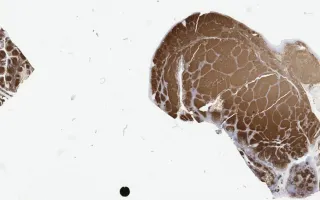

Lymph Nodes, Follicular lymphoma, CD20 stain

This slide shows CD20 stain. See Related Content for H&E, CD10, BCL6, and BCL2 stains.

Immunohistochemistry studies demonstrated that the neoplastic cells were positive for CD20, CD10, BCL-2 and BCL-6 (see related content). They were negative for CD3, CD5, CD23, CD43 and cyclin D1 (not shown). CD21 revealed the presence of a follicular dendritic cell meshwork (not shown).

Sections in this case show effacement of the lymph node architecture by an abnormal lymphoid proliferation with nodular pattern. There is an average of more than 15 centroblasts per 40x high power field amongst centrocytes. The follicular architecture is maintained throughout. No sheeting or clusters of centroblasts are identified.